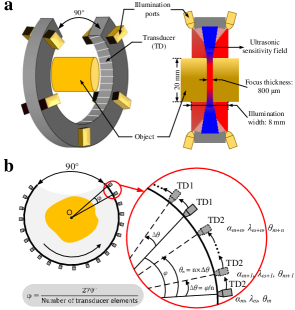

All experiments are conducted using a commercial multispectral PAT platform (MSOT inVision128, iThera Medical GmbH, Germany). The system employs a ring transducer array comprising 128 elements and a radius of 40.5 mm. The transducer elements have a central frequency of 5 MHz. The system is equipped with a pulsed optical parametric oscillator (OPO) laser (SpotLight 600, InnoLas, Germany), capable of emitting pulsed laser light ranging from 680 nm to 980 nm. The laser pulses are emitted through 10 irradiation ports, ensuring a uniform distribution of laser energy across the surface of the imaged object. The laser operates at a pulse repetition frequency of 10 Hz, with a wavelength switching time of 30 ms. When irradiating a cylindrical sample with a diameter of 20.0 mm, the laser creates a ring-shaped illumination with a width of 8.0 mm on the sample’s surface, as shown in Fig.3 (a).

To showcase the effectiveness of the U3S-PAT method, the imaging configuration of the U3S-PAT scheme is simulated by leveraging a densely sampled dataset acquired by our MSOT system. By selectively retaining the signals acquired only at the sparse transducer locations and discarding the remaining densely sampled data, the spirally scanned and sparsely sampled data can be obtained. We use wavelengths for U3S-PAT in all our experiments, including 700 nm, 730 nm, 760 nm, 800 nm and 850 nm. We perform separate image reconstructions for two distinct numbers of transducer elements. As shown in Fig.3 (b), one transducer array consists of elements, corresponding to an element down sampling rate of 1/6, with a rotation angle of per step. The other transducer array consists of elements, corresponding to an element down sampling rate of 1/8, with a rotation angle of per step. With the above setup, the fused prior image used during image reconstruction covers the whole angular spacing.

In the U3S-PAT imaging system, the transducer array is horizontally translated and rotated during the scanning process. The translation distance in spectral unmixing experiments, also known as the slice spacing, is set to 0.5 mm, which is smaller than the 800 m focus detection sensitivity field of the laser. This scheme ensures that anatomical information is shared between neighboring images. While the translation distance in the image reconstruction experiments is set to 1.0 mm, because the focal zone of each transducer element is characterized by the -6 dB zone (i.e. the area in which the sensitivity drops to half its maximum value), and the actual detection region is larger than the focus detection sensitivity region.